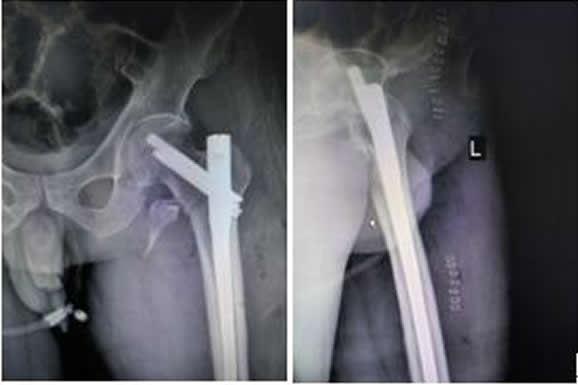

患者劉某某,男,70歲,以“左髖摔傷疼痛活動(dòng)受限2小時(shí)余”之主訴于2016.9.26入院。入院診斷:左股骨近端粉碎骨折。患者于2016.9.30上午硬腰聯(lián)合麻醉下行骨折閉合復(fù)位InterTan內(nèi)固定術(shù)。手術(shù)順利,術(shù)后患者恢復(fù)良好,現(xiàn)已出院。術(shù)后復(fù)查拍片如下:

左髖關(guān)節(jié)正側(cè)位X線(xiàn)片